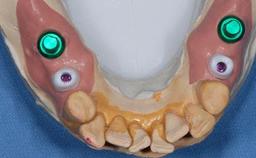

The patient presented with a failing tooth-supported fixed dental prosthesis with cantilever extension replacing the right maxillary central incisor. His chief presenting complaint was poor esthetics, in particular the dark discolored margin around the abutment tooth, the maxillary left central incisor. He reported a history of trauma at a young age, which necessitated the replacement of his maxillary right central incisor as well as root canal therapy of the adjacent left central incisor. The existing prosthesis had been in situ for over 20 years. The initial periapical radiograph displayed good proximal bone levels at the adjacent teeth and a wide incisive canal, which was a concern. The left central incisor presented a very wide root canal treatment with compromised radicular dentin thickness, which was a consideration in the decision between a new tooth-supported fixed dental prosthesis vs. an implant-supported prosthesis. After a lengthy discussion on the risks and benefits of both treatment options, the patient decided on a single-tooth implant replacement.

Prosthesis Type FDP